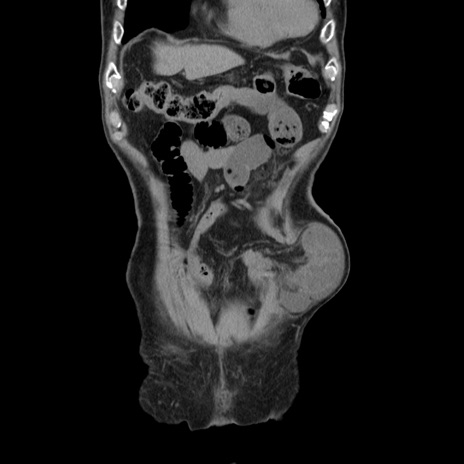

症例24(冠状断像)

矢状断像